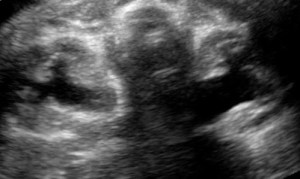

Bilateral hydronephrosis.